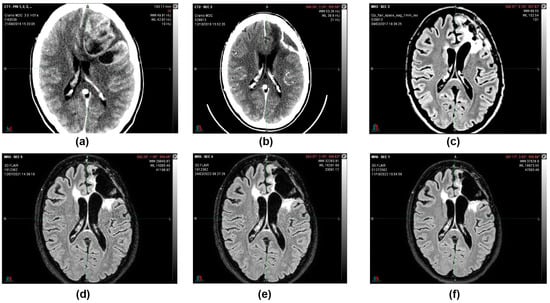

In August 2016, in the emergency department, a 36-year-old woman, after 15 days of headache and unresponsiveness to non-steroidal anti-inflammatory drugs (NSAID), underwent a computed tomography scan (CT scan). The CT scan of the brain, performed with contrast medium, showed, in the left fronto-parietal area, two voluminous formations and inhomogeneous contiguous focalities of 52 × 41 mm and 40 × 20 mm, respectively, characterized by irregular peripheral impregnation and contextual necrotic–colliquative areas, with surrounding perilesional digitiform hypodensity, compression of the lateral ventricle, and contralateral shift of the midline structures (1 cm) (Figure 1).

Figure 1.

Computerized tomography (CT) scan with contrast medium performed at initial diagnosis (21 August 2016) showed, in the left fronto-parietal area, two voluminous formations and inhomogeneous contiguous focalities of 52 × 41 mm and 40 × 20 mm, respectively, characterized by irregular peripheral impregnation and contextual necrotic-colliquative areas, with surrounding perilesional digitiform hypodensity, compression of the lateral ventricle, and contralateral shift of the midline structures (1 cm).